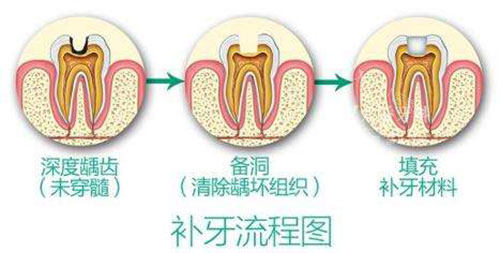

确定好方案后,就开始补牙了。我心里那叫一个紧张啊,紧紧地攥着拳头。张医生好像看出了我的紧张,一边操作一边跟我聊天,分散我的注意力。在打麻药的时候,他手法特别轻,就感觉有那么一点点疼,完全在能忍受的范围之内。等麻药起作用后,处理蛀牙的过程我基本没啥感觉。张医生的技术那叫一个娴熟,没一会儿就把龋坏的部分清理干净了,然后开始补牙。补完后,还反复帮我调整咬合,确保我牙齿咬起来舒服。整个补牙过程也就半个多小时,比我想象中快多了。